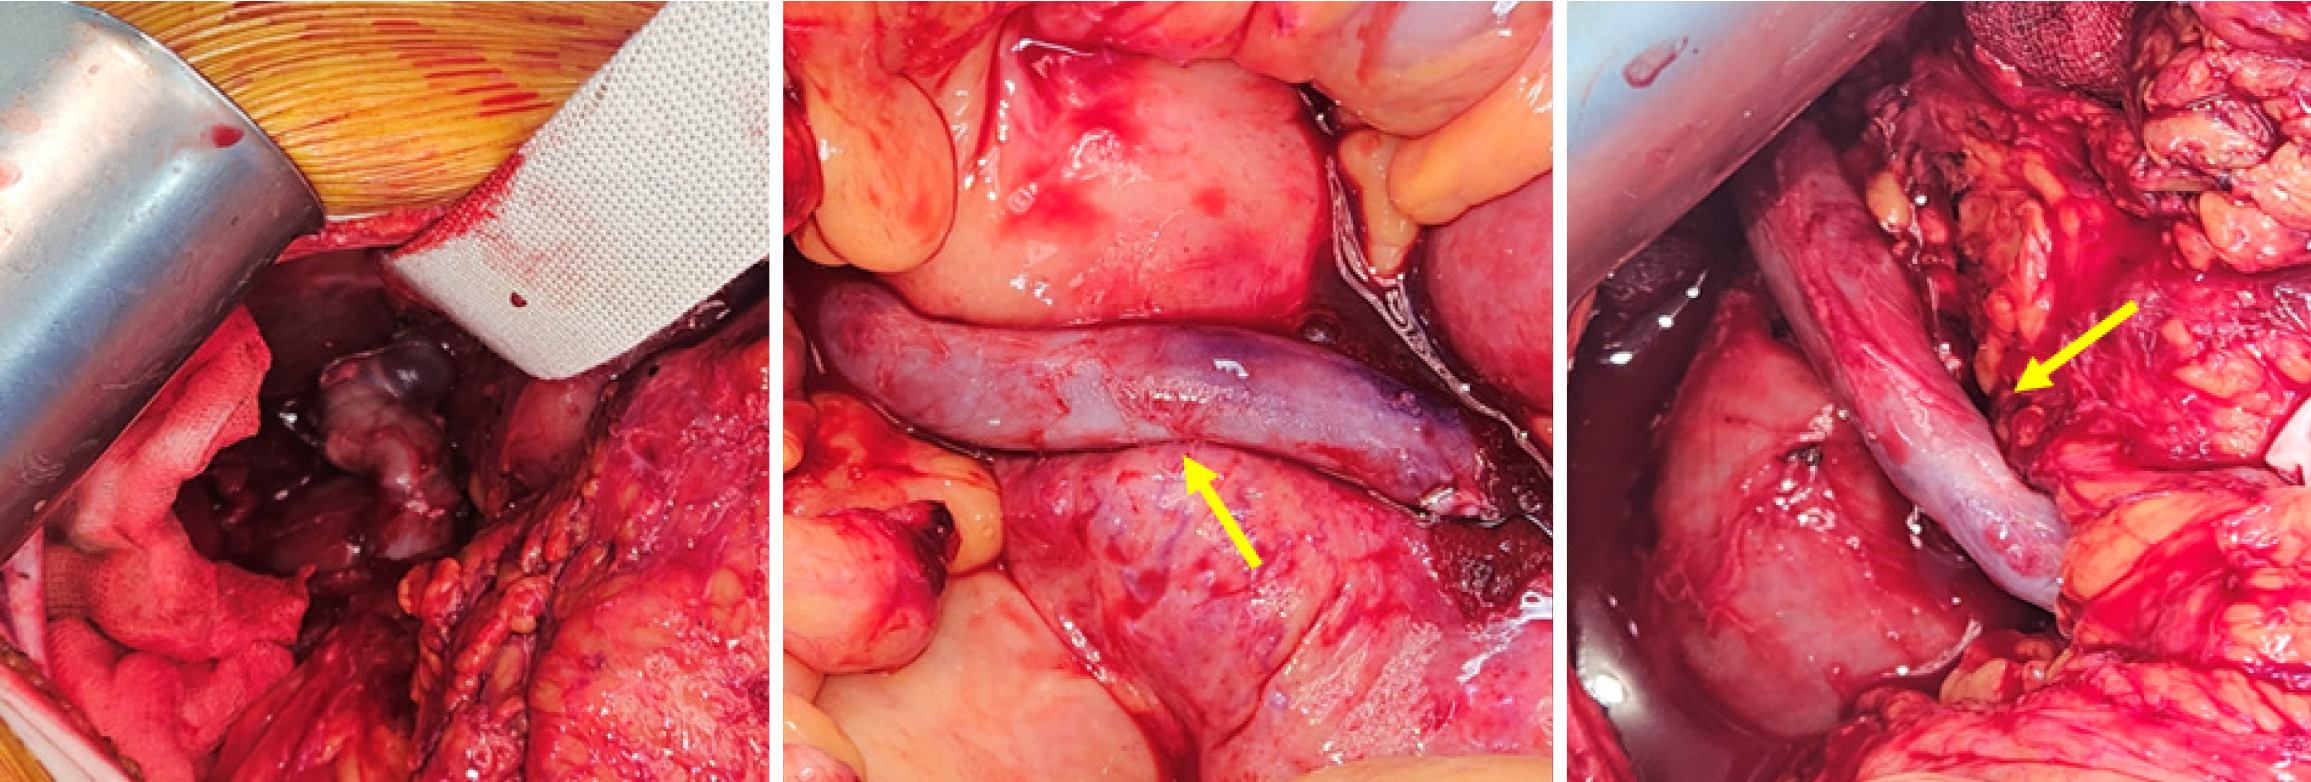

Figure 4 Intra-abdominal vein bypass surgery.

There was upstream thrombosis and severe stricture and portal vein side wall was exposed for side-to-side anastomosis both side with cadaveric iliac vein graft (arrow).